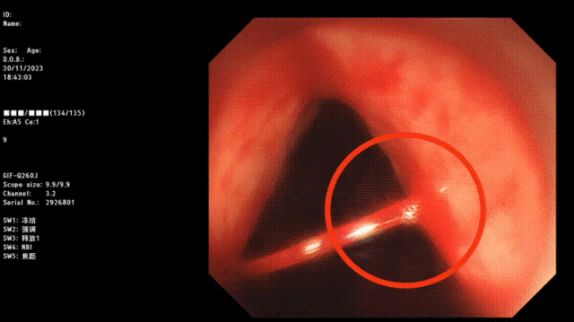

image.png

止血成功